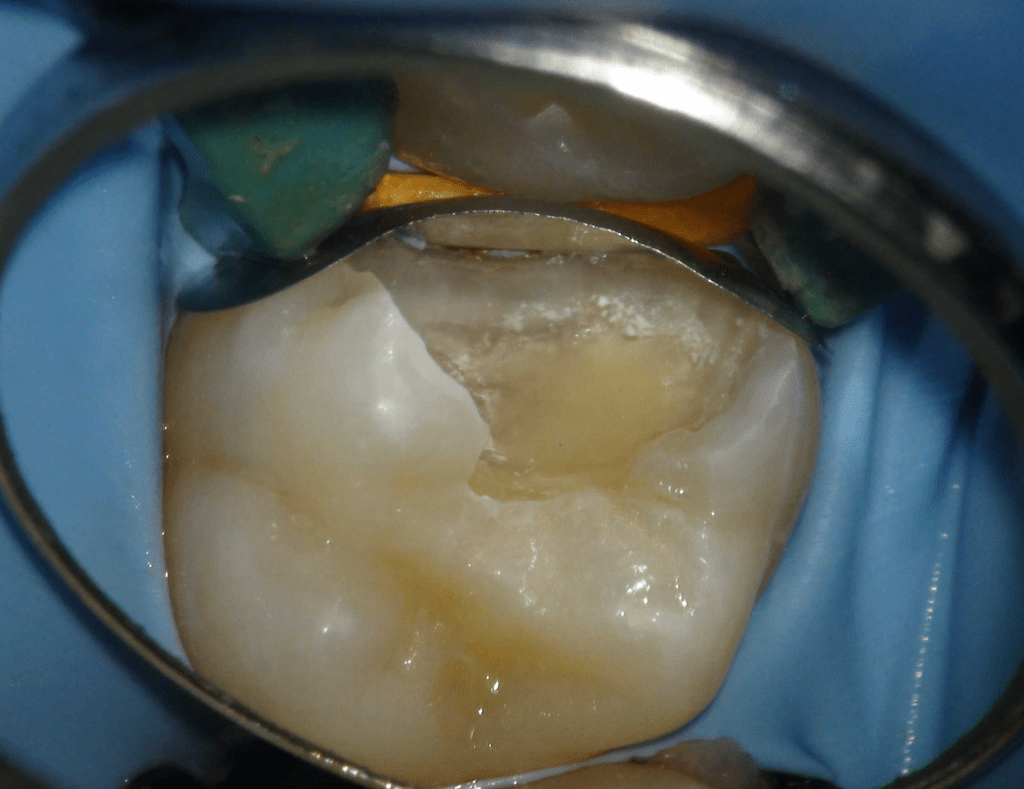

Pulpotomía biodentine + reco preendio